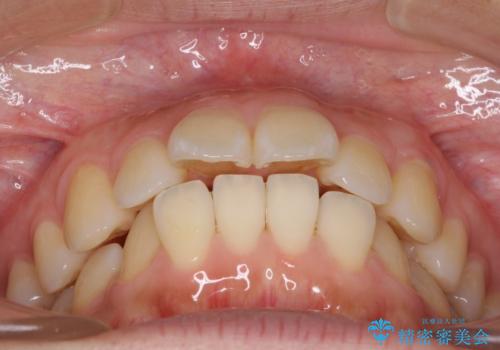

前に出ている前歯を引っ込めたい インビザライン矯正

- 前方に傾斜した上下の前歯を気にして来院された患者様です。

唇の閉じにくさや横顔のシルエットが気になるような突出感ではなかったため、インビザラインを用いて、歯列の遠心移動とIPR(歯と歯の間を削る)により前歯の傾斜を改善していくこととしました。

スムーズに終了すると思われましたが、インビザライン矯正独特の奥歯が咬み合わない状態が続き、更には遠方へ転居されたこともあり、治療期間は長引いてしまいました。